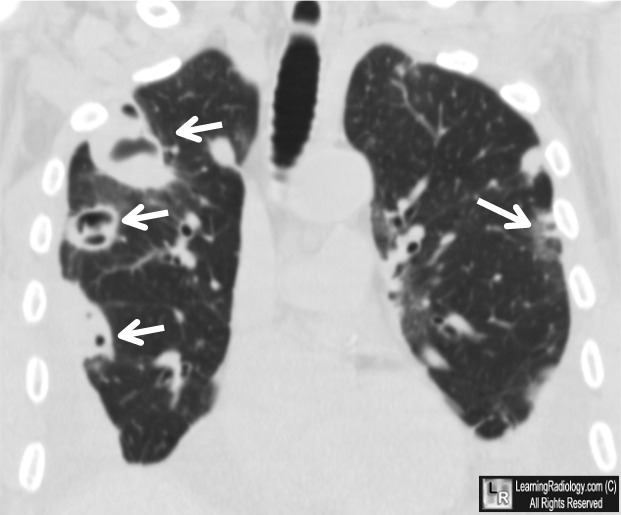

From www.learningradiology.com

LearningRadiology Septic Emboli Treatment Determine the management of acute embolic stroke. Identify the underlying etiology of embolic strokes. Septic embolism is an infection in a blood vessel that can block blood flow and cause abscesses. Identify the epidemiology of embolic stroke. Septic embolism is an obstruction of a blood vessel, typically by an infected thrombus that travels through the. Learn about the sources, clinical. Septic Emboli Treatment.

LearningRadiology Septic, Pulmonary Emboli, embolus, embolism Septic Emboli Treatment Learn about the symptoms, causes, diagnosis, treatment, and outlook of this. Identify the underlying etiology of embolic strokes. However, sometimes antibiotics are not completely effective and, in some cases,. Determine the management of acute embolic stroke. Septic embolism is an infection in a blood vessel that can block blood flow and cause abscesses. Treatment for septic embolism includes antibiotics to. Septic Emboli Treatment.

Pulmonary Septic Emboli seen on CT Chest. Download Scientific Diagram Septic Emboli Treatment Treatment for septic embolism includes antibiotics to target the bacteria. Septic emboli are infections that travel to distant organs via the bloodstream, causing tissue damage and sepsis. Learn about the sources, clinical presentation, investigations and treatment. Identify the epidemiology of embolic stroke. Septic embolism is an infection in a blood vessel that can block blood flow and cause abscesses. Identify. Septic Emboli Treatment.